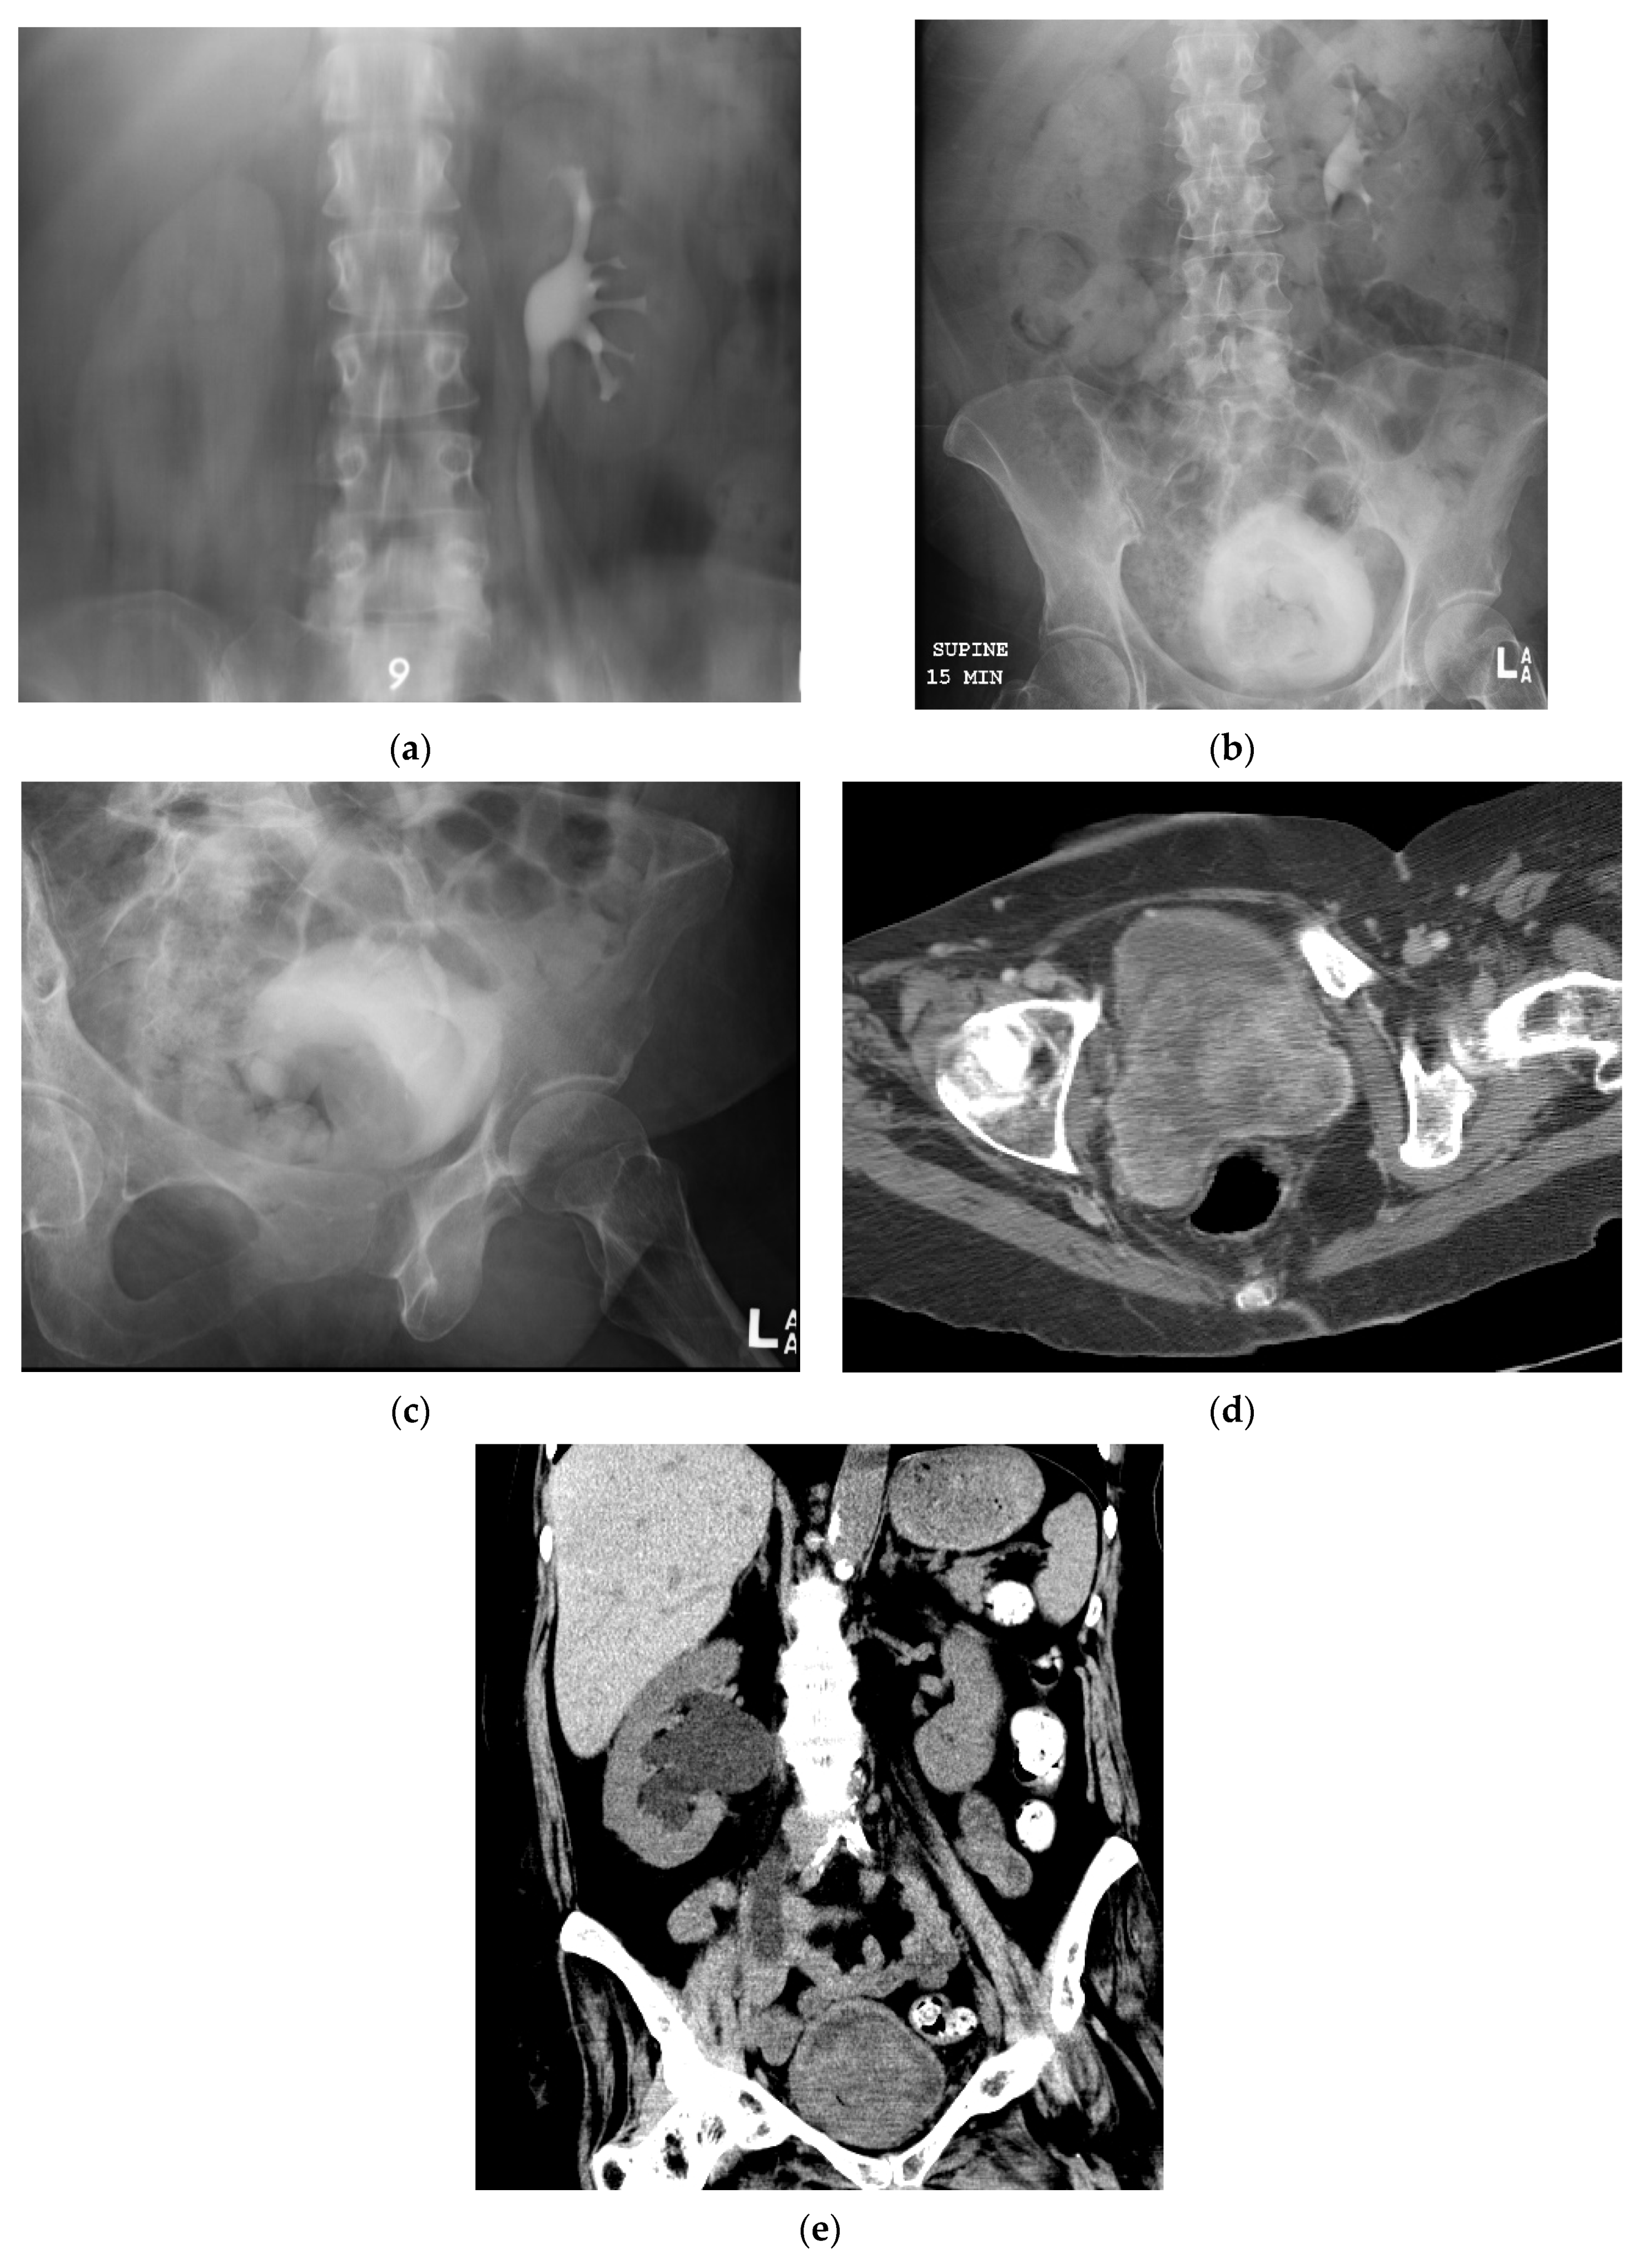

5.1. Computed Tomography (CT)

5.5. Fluoroscopic/Radiographic Techniques